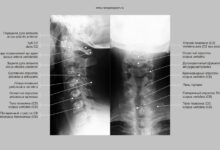

Для более точного выявления заболеваний печени используются инструментальные методы диагностики. Они позволяют увидеть структурные изменения и опухоли в органе.

Среди основных инструментальных методов выделяют:

- Ультразвуковое исследование печени

- Компьютерная томография (КТ)

- Магнитно-резонансная томография (МРТ)